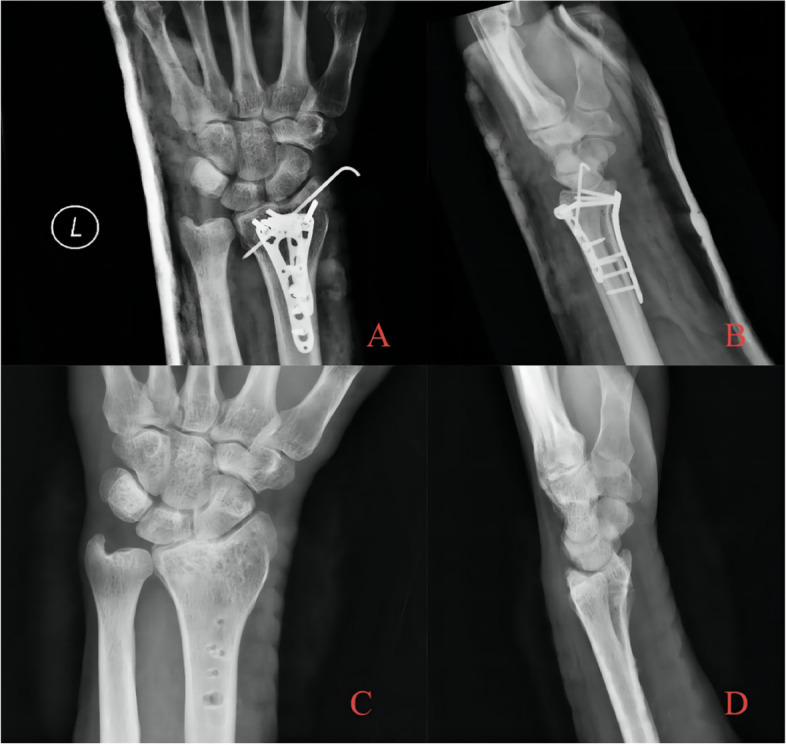

Fig. 2.

A 38-year-old patient with die-punch DRF. Radiography data showed a die-punch fracture of the left distal radius and a fracture of the articular surface of the intermediate column with obvious displacement. A AP radiography; B Lateral radiography; C Axial view of the articular surface of the radius. The fractures involved the articular surface of the intermediate column and lateral column; D Coronal plane, collapse of the lunate articular surface is obvious; E Sagittal plane, bone fragment shifted to the dorsal side; F Three-dimensional reconstruction of the CT image

Fig. 3.

After satisfactory reduction, locking plates were used on both the dorsal and palmar sides. Kirschner wires for auxiliary fixation were retained for 8 weeks and were removed afterwards. The surgical results were good. The long-term follow-up after 30 months showed that the height of the articular surface was well maintained, and there was no obvious collapse of the articular surface. The internal fixator was removed for patient A Immediate postoperative AP radiography; B Immediate postoperative lateral radiography; C AP radiography after removal of internal fixation with follow-up over 30 months. Radial height was well maintained, and the articular surface was congruent in general; hence, no obvious articular step-off developed. D Lateral radiography after removal of internal fixation